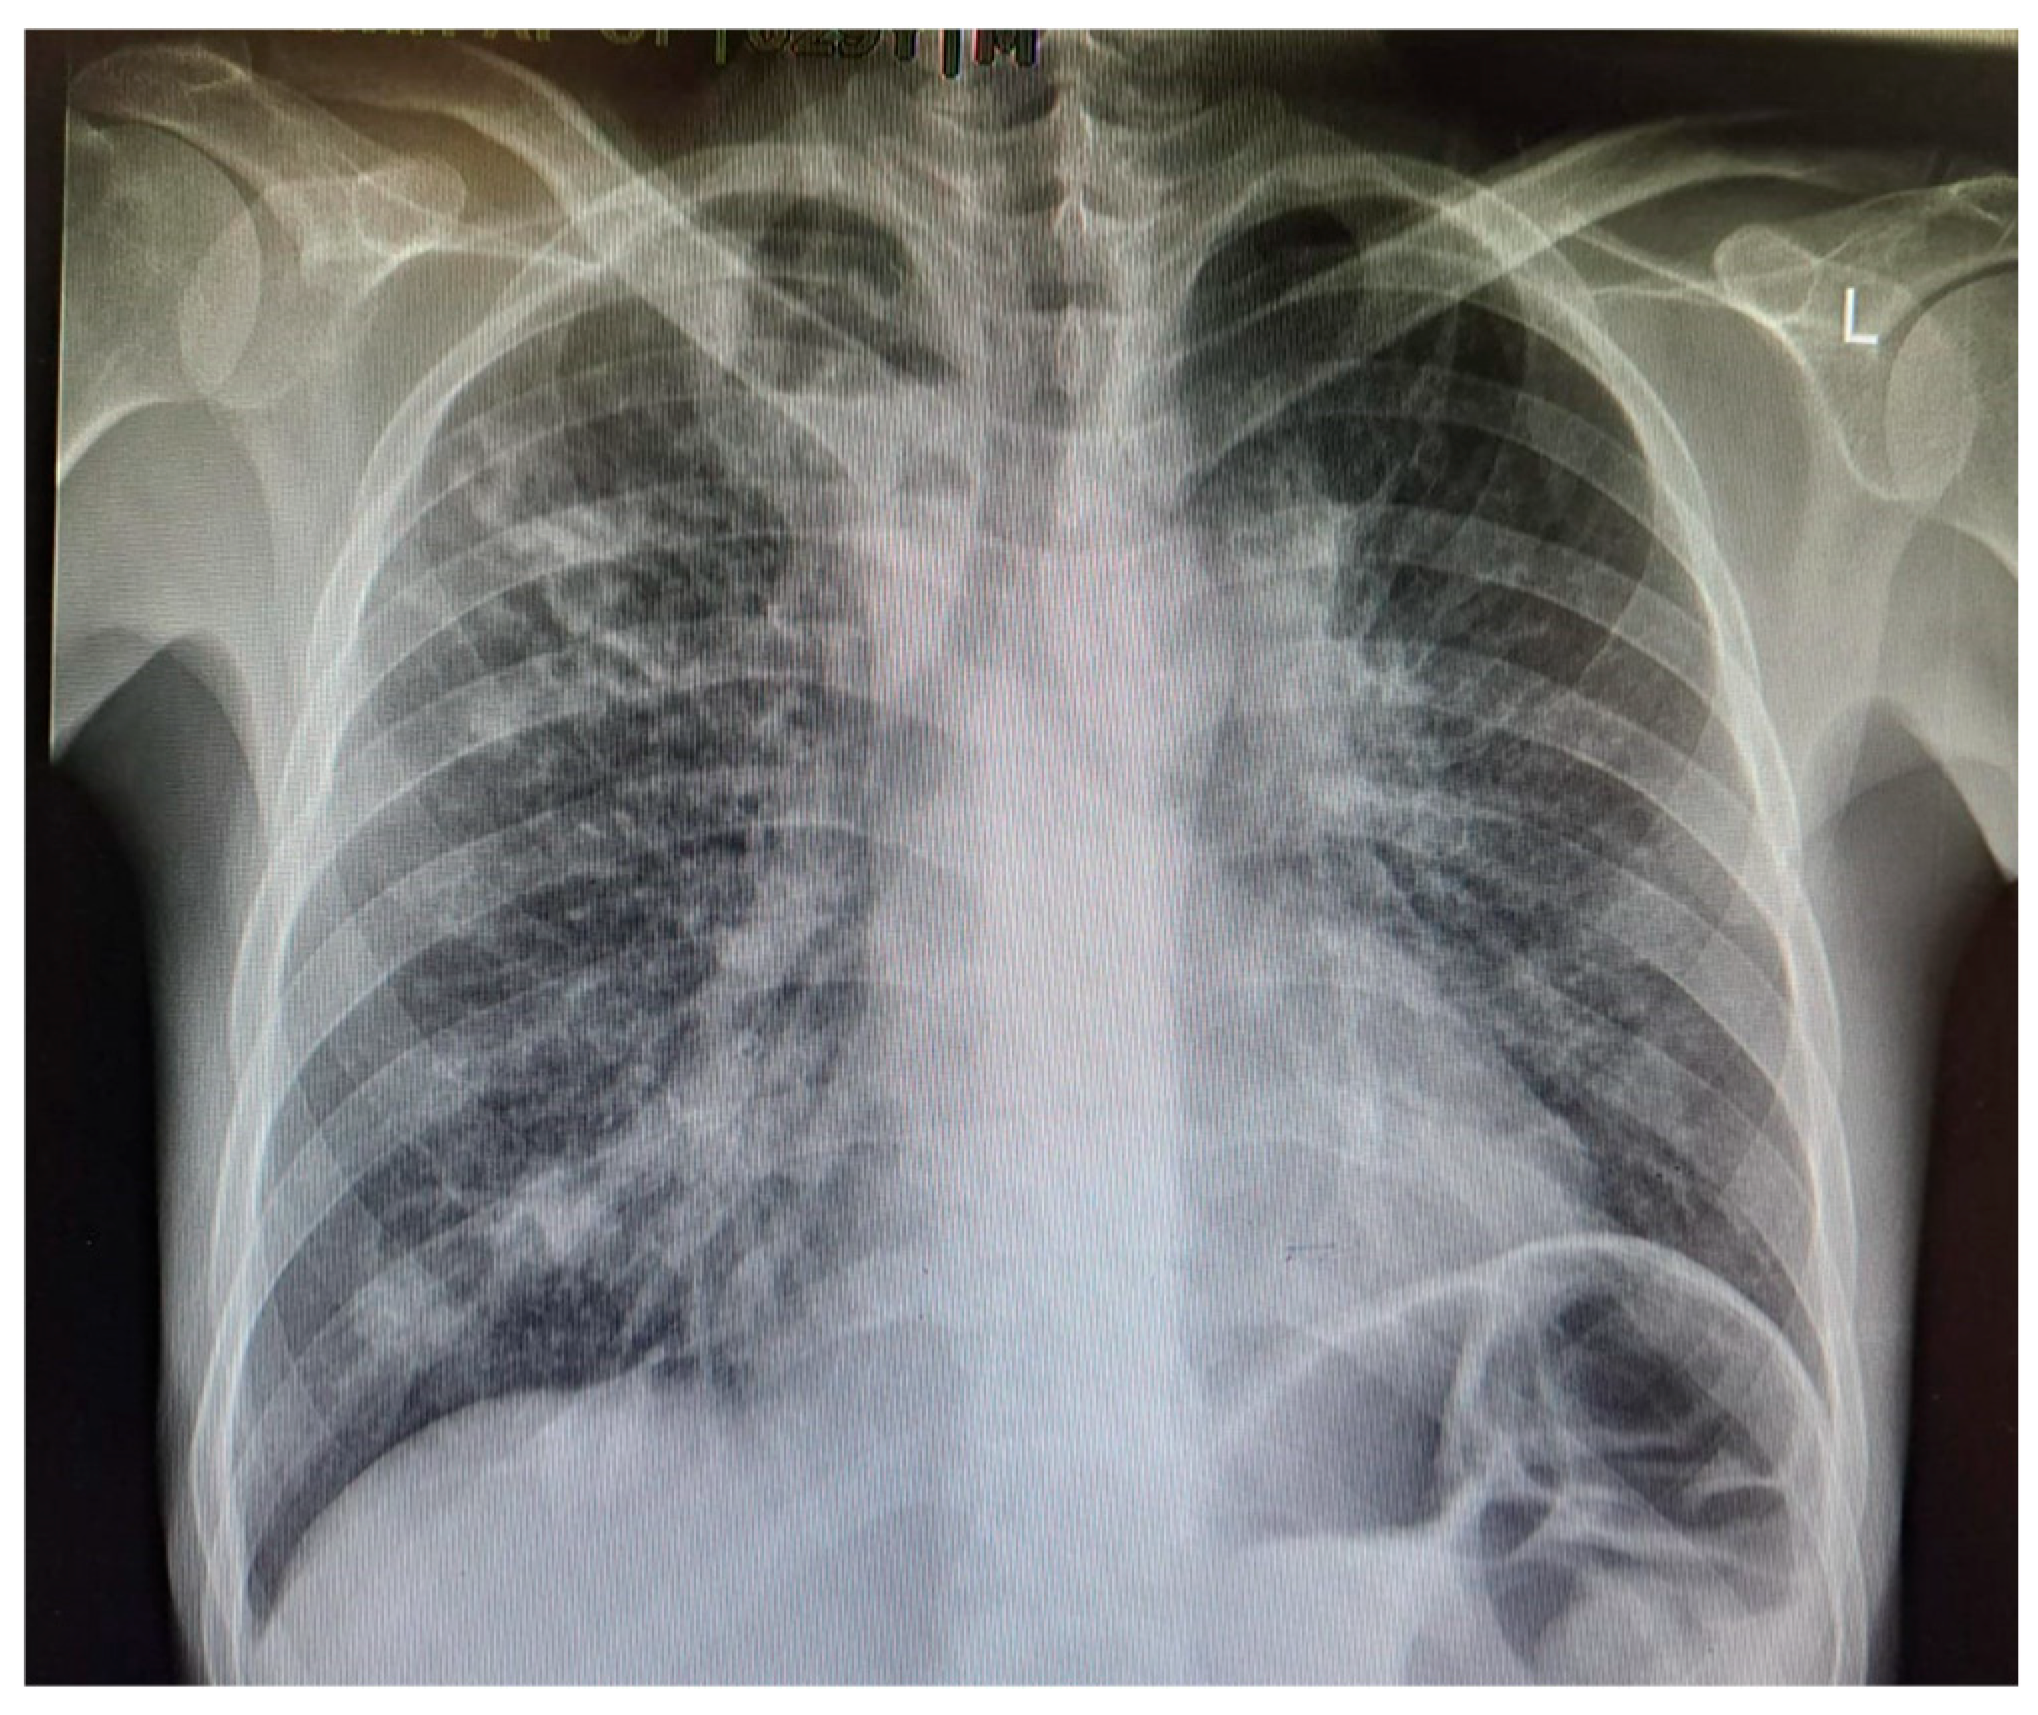

M. tuberculosis infection often leads to injury to the pleura. This includes the thickening and fibrosis of the pleura, and in many of these cases, patients further form calcification. About 40.9% of patients with fibrosis form these calcifications, as demonstrated in a CT-based study by Deshpande et al. [9]. The presence of fibrosis often results in decreased lung capacity on one side of the chest. This can be due to the cavities that form within the lungs as a result of the infection. In patients who had a single cavity in their lungs, fibrosis was found 100% of the time and calcification 80% of the time. In addition, 90% of these single cavities were found in the upper lobes of the lungs [9]. Upper lobe damage to the lungs can be seen in Figure 2. Further evidence of the presence of M. tuberculosis can be observed in Figure 3, in which many acid-fast bacilli are shown. The consistent presence of fibrosis and calcification in these cases suggests prolonged infection. This represents the host’s attempt to contain the mycobacterial focus. Fibrosis may contribute to disrupted lung structure and functional impairment of the lung, while calcification often marks the healing or inactive phase of a granulomatous lesion.

Figure 2. Chest X-ray of a 29-year-old male with active TB, showing bilateral upper lobe opacities and cavitation, consistent with advanced pulmonary TB. These findings reflect extensive lung parenchymal damage due to the infection.